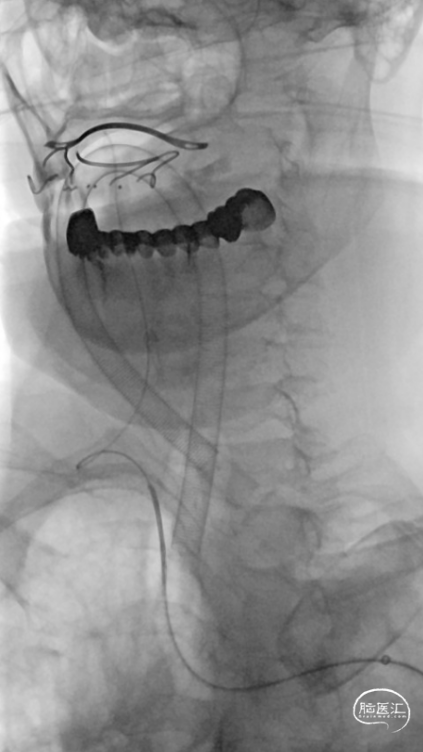

患者血管路径迂曲,经Simon2导管采用交换技术将8F导引导管内衬多功能导管,反复尝试均无法进入RCCA,后更换为Super Stiff导丝支撑,将8F导引导管送至RCCA远端。

将Catalyst7 132中间导管经导引导管送至于RICA C1段起始部闭塞处,采用ADAPT技术自C1段至C4段反复抽吸取栓,取出大量暗红色血栓。

手推冒烟见RICA C1-C5段显影,C5段以远闭塞。将Pro-18微导管在Synchro(0.014×200mm)微导丝引导下送至RMCA M2段,微导管冒烟示远端血流通畅。将Trevo XP(4×20mm)取栓支架于M1段远端向RICA末端释放,采用SWIM技术取栓1次,并同时将中间导管送至颈内动脉末端抽吸。抽出数枚暗红色血栓。